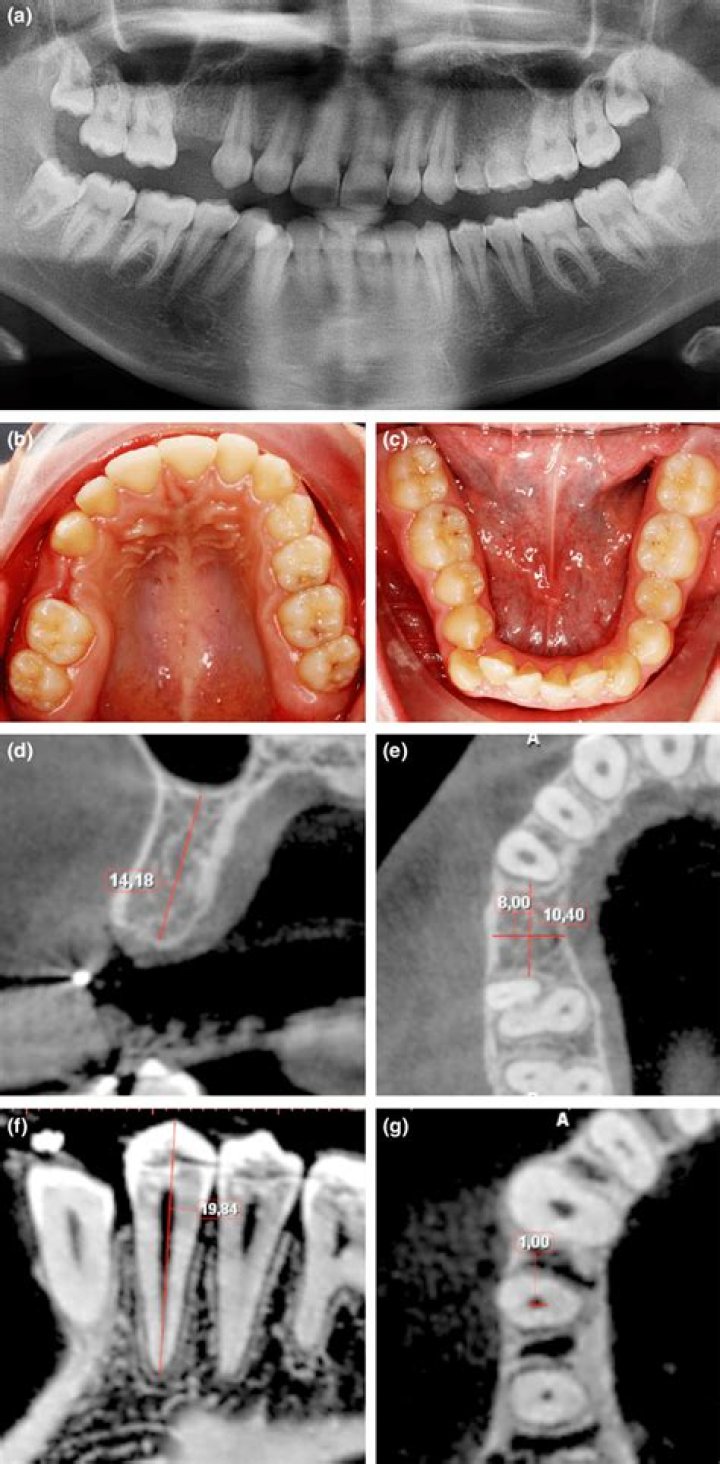

Hypodontia is genetic in origin and usually involves the absence of from 1 to 5 teeth. Oligodontia is genetic as well and is the term used to describe a c...